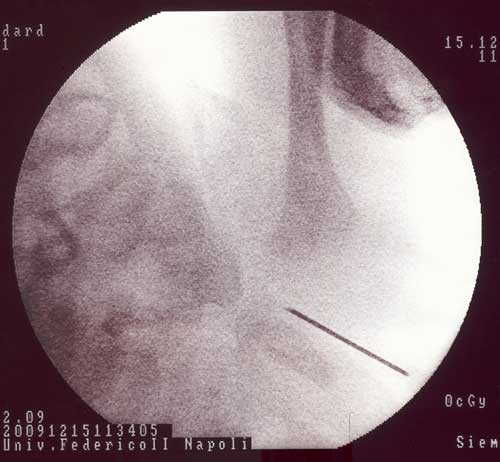

Nell�ipotesi di un�osteo-artrite settica, consapevoli della importanza di una terapia tanto tempestiva quanto aggressiva per ridurre al minimo il rischio di gravi esiti a distanza e considerata la possibile etiologia a questa et� (S. aureus, Streptococco di gruppo B, E. coli, Haemophylus influentiae ecc.), viene programmata atrocentesi (praticata 24 ore dopo) (Figura 4) e immediatamente iniziata terapia antibiotica e.v.: teicoplanina 16 mg/kg/die, ampicillina-sulbactam 150 mg/kg/die, netilmicina 7 mg/kg/die fino all�esito della coltura del liquido articolare (dopo 10 gg, sterile); successivamente la terapia � proseguita e.v. soltanto con teicoplanina e netilmicina per un totale di 4 settimane1,2.

Figura 4. Artrocentesi